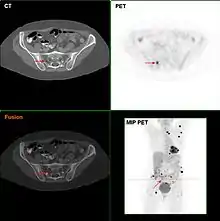

Metastatic melanomas can be detected by X-rays, CT scans, MRIs, PET and PET/CTs, ultrasound, LDH testing and photoacoustic detection.[90] However, there is lack of evidence in the accuracy of staging of people with melanoma with various imaging methods.[91]

It is common for patients diagnosed with melanoma to have chest X-rays and an LDH test, and in some cases CT, MRI, and/or PET scans. Although controversial, sentinel lymph node biopsies and examination of the lymph nodes are also performed in patients to assess spread to the lymph nodes. A diagnosis of melanoma is supported by the presence of the S-100 protein marker.